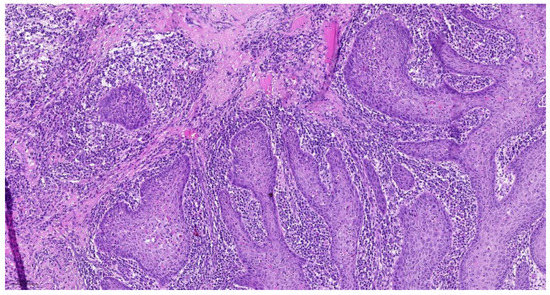

2.3. Cellular Dissociation Grade (CDG)

| Tumor Budding * (TB) | No tumor budding | Score 1 |

| 1–5 tumor buds/HPF | Score 2 | |

| >5 tumor buds/HPF | Score 3 | |

| Cell Nest Size (CNS) | >15 cells per nest 5–15 cells per nest 2–4 cells per nest | Score 1 Score 2 Score 3 |

| single cell invasion | Score 4 | |

| Cellular Dissociation Grade (CDG) | Sum TB + CNS = 2–3 Sum TB + CNS = 4–5 | CDG-1 CDG-2 |

| Sum TB + CNS = 6–7 | CDG-3 |